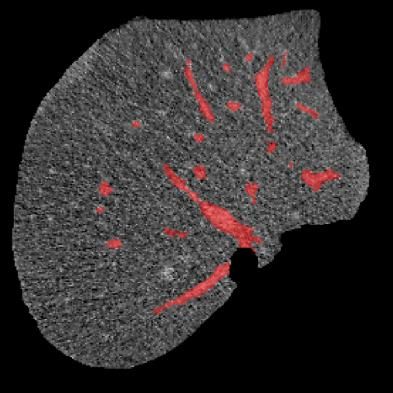

Manually segmenting the hepatic vessels from Computer Tomography (CT) is far more expertise-demanding and laborious than other structures due to the low-contrast and complex morphology of vessels, resulting in the extreme lack of high-quality labeled data. Without sufficient high-quality annotations, the usual data-driven learning-based approaches struggle with deficient training. On the other hand, directly introducing additional data with low-quality annotations may confuse the network, leading to undesirable performance degradation. To address this issue, we propose a novel mean-teacher-assisted confident learning framework to robustly exploit the noisy labeled data for the challenging hepatic vessel segmentation task. Specifically, with the adapted confident learning assisted by a third party, i.e., the weight-averaged teacher model, the noisy labels in the additional low-quality dataset can be transformed from "encumbrance" to "treasure" via progressive pixel-wise soft-correction, thus providing productive guidance. Extensive experiments using two public datasets demonstrate the superiority of the proposed framework as well as the effectiveness of each component.